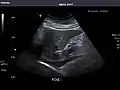

Abdominal Ultrasound (Full Exam)

STRUCTURED REPORT

(Technique: Transabdominal ultrasonography; Device: Toshiba Aplio XG)

Liver: Diffusely homogeneous and normal in echogenicity. No focal mass or contour nodularity. No intrahepatic biliary ductal dilatation.

Portal Vein: Patent main portal vein.

Gallbladder: No stones, wall thickening, or pericholecystic fluid.

Common Bile Duct: Nondilated measuring 1.3 mm at the level of the porta hepatis.

Pancreas: Visualized portions unremarkable.

Spleen: Normal in size.

Kidneys: Right and left kidneys measure 11.5 cm and 12 cm in length respectively. No hydronephrosis. Small left lower pole kidney cyst.

Ascites: None.

Aorta: Visualized portions normal in caliber, 16 x 15 mm.

IVC: Normal.

IMPRESSION:

Normal abdominal ultrasound.